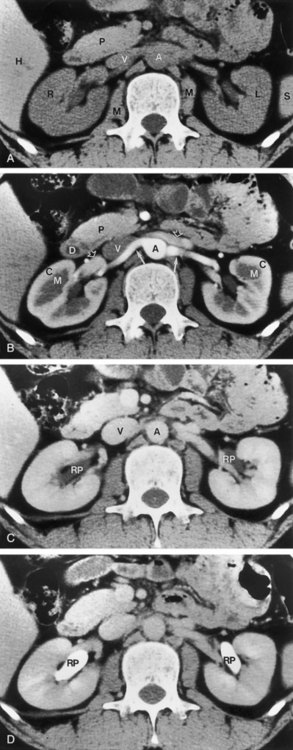

Measuring bladder wall thickness may assist the clinician in understanding the degree of bladder outlet obstruction (Fig. 4–37). Bladder wall thickness varies depending on the volume of urine in the bladder and on which part of the bladder wall is measured. It has been shown that measuring bladder wall thickness may predict bladder outlet obstruction with greater accuracy than free uroflowmetry, postvoid residual urine, and prostate volume (Oelke et al, 2007).

Figure 4–37 Bladder wall thickness may provide information about bladder outlet obstruction. In this sagittal view, bladder wall thickness is measured posteriorly (arrow) near the midline. Note the trabeculation of the relatively hyperechoic bladder wall.

Transabdominal prostatic ultrasonography requires angling the probe beneath the pubic bone. In the transverse plane the transducer is fanned inferiorly until the largest transverse diameter of the prostate is identified. Measurements of the transverse width and height are obtained (Fig. 4–38A). The transducer is then rotated 90 degrees clockwise to produce a true sagittal image of the prostate. The transducer is fanned until the midline is identified. This is recognized by a v-shaped indention at the bladder neck (Fig. 4–38B). Depending on the degree of prostatic hypertrophy and the presence or absence of a middle lobe, this “v” may be more or less apparent and more or less anterior or posterior in its position. A sagittal measurement is made from the bladder neck to the apex of the prostate. The apex of the prostate may be identified by using the hypoechoic urethra as a guide.

Figure 4–38 A, Transabdominal ultrasound is extremely useful for measuring prostatic volume and evaluating prostatic morphology. The volume of the prostate can be calculated using this formula: prostate volume (mL) = width (cm) × height (cm) × length (cm) × 0.523. B, In this midsagittal view of the prostate, the bladder neck is identified as a V-shaped indentation (arrow). Note the characteristically hyperechoic trigone (arrowhead).